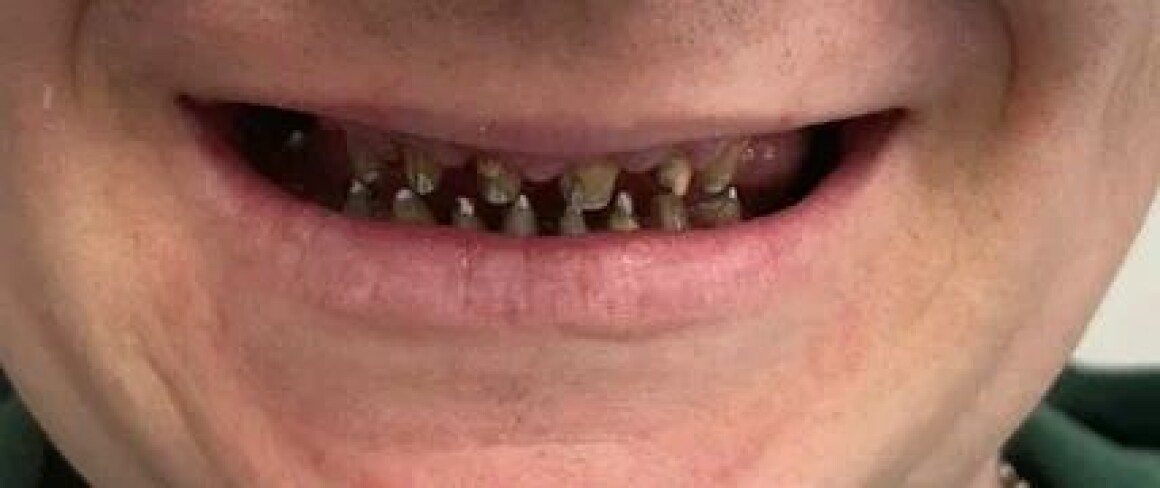

Проблема : Полное отсутствие зубов, не держаться протезы

• Установка временных коронок на имплантантах